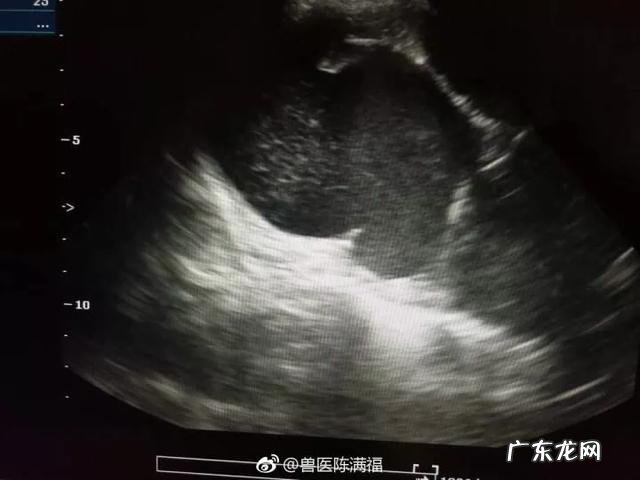

B超下的子宫蓄脓